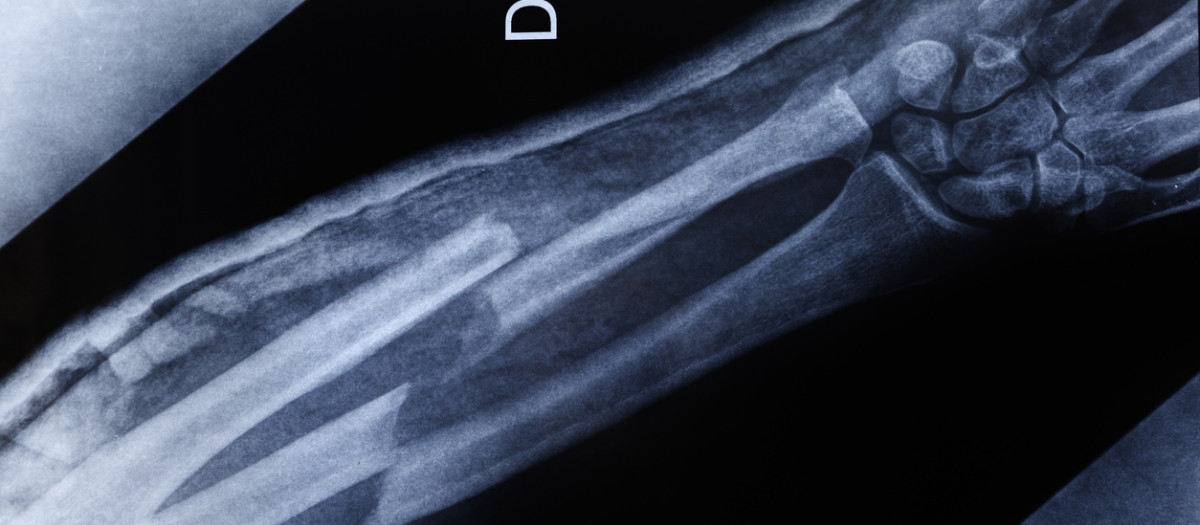

Imagen de rayos X de un brazo fracturado

Imagen de rayos X de un brazo fracturadoGetty Images / David Pedre

Este nuevo biomaterial, bautizado como «Bone 02», demostró una eficacia y seguridad sobresalientes en el tratamiento de fracturas conminutas -aquella en la que un hueso se rompe en tres o más fragmentos-. El estudio incluyó a más de 150 pacientes y todos los indicadores clínicos alcanzaron los estándares previamente establecidos.